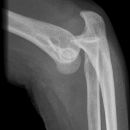

Fat Pad Sign

nicht dislozierte Radiusköpfchenfraktur